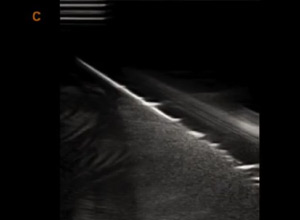

Компрессионная эластография с количественной оценкой Strain

Компрессионная эластография

Цветовое картирование жесткости тканей с количественным анализом Strain Ratio. Режим работает на конвексных, линейных, внутриполостных и микроконвексных датчиках.

Улучшенная биопсия.

Режим улучшенного отбражения биопсийной иглы на линейном датчике за счёт применения подсветки дополнительным ультразвуковым лучом. Для биопсии аппарат также поддерживает стальные многоразовые биопсийные насадки, пункционные экранные линии (с возможностью произвольной настройки), а также центральную осевую линию на экране.